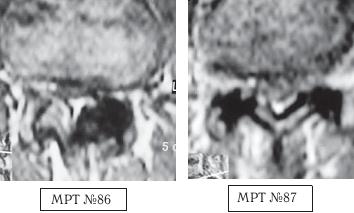

МРТ № 2

На МРТ № 2 — грудной отдел в состоянии «норма»

Грудной отдел должен иметь нормальную степень кифоза (угол кифоза по Stagnara формируется линией, параллельной замыкательным пластинкам ТIII и ТXI= 25°). Позвоночный канал на грудном уровне имеет округлую форму, что делает эпидуральное пространство узким почти по всей окружности дурального мешка (0,2–0,4 см), а на участке между TVI и ТIX он наиболее узок. Сагиттальный размер: ТIХI = 13–14 мм, ТXII = 15 мм. Поперечный диаметр: > 20–21 мм.

Высота межпозвонковых дисков: самая меньшая на уровне ТI, на уровне ТVIХI приблизительно 4–5 мм, наибольшая на уровне ТХIХII.